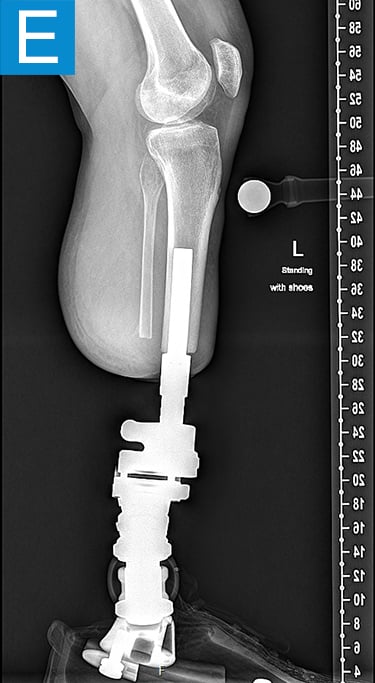

His first surgery was the transtibial amputation with simultaneous osseointegration. This entailed performing amputation of the tibia and fibula at the planned level, reaming and broaching the tibial canal to achieve a uniform canal for the diameter and length of the implant and inserting the osseointegration implant. This feels similar to how a cementless total hip femur implant mixed with an intramedullary nail might feel. Phantom nerve pain was prevented via regenerative peripheral nerve interface technique. Then the skin around the implant that passed through the skin portal was closed. His recovery followed the standard protocol of 4 weeks non-weightbearing followed by 4 weeks of progressive loading, with the prosthesis attached at 2 months (Figure 2). He quickly achieved a better gait than he had prior to amputation (Video 2) with essentially equal swing and stance per leg, but lateral knee pain persisted. Four months after osseointegration, a distal femur osteotomy was performed to neutralize his alignment.

Figure 2. Postoperative clinical photos and radiographs. (A) Front and (B) rear views show the patient standing with the osseointegrated tibia prosthesis. (C) Photo shows stable and healthy skin at portal site to be, although slightly dry due to the winter weather. The gold-colored metal is part of the permanent transcutaneous implant; the shiny silver-colored metal beneath the gold is part of the clinician-removable prosthesis connector, and the matte silver metal beneath features a screw at the front, by which the patient secures the prosthesis. (D) Standing coronal radiograph depicts residual genu valgum in the osseointegrated leg. (E) Lateral radiograph of the osseointegrated tibia. (F) Coronal radiograph of the left knee shows the distal femur osteotomy. (G) Final coronal radiograph after distal femur plate and screw removal shows well-aligned left leg with osseointegrated prosthesis.